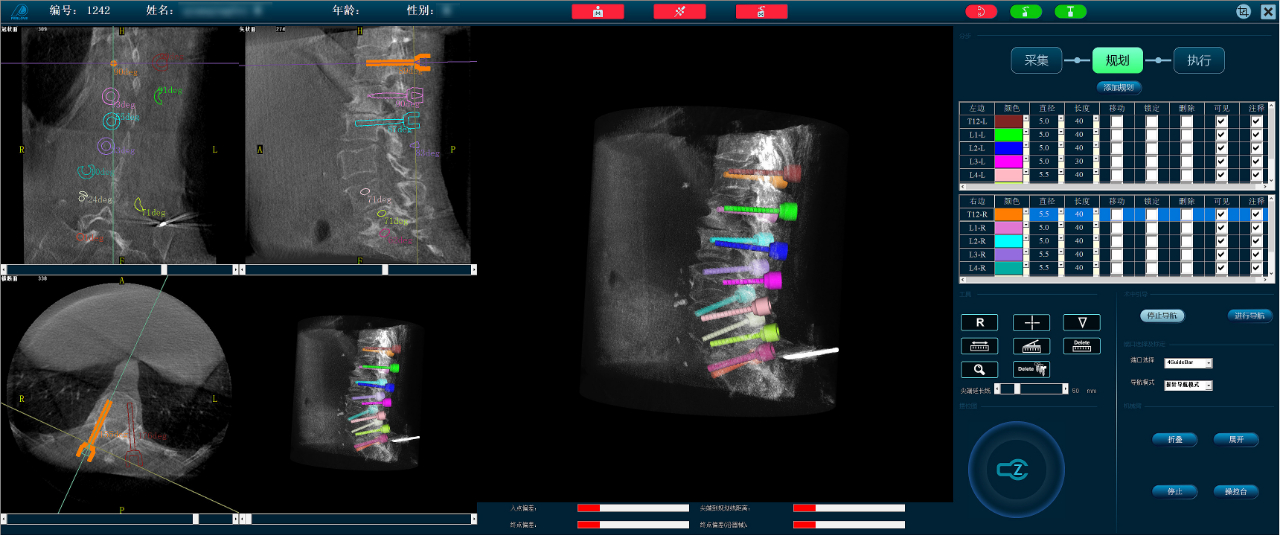

Precise Planning of 14 Screws in One Go Utilizing the Perlove Medical 3D C-arm system, intraoperative three-dimensional images were obtained and transmitted to the orthopedic surgical robot workstation. Using surgical planning software, the surgeon precisely planned the positioning of 14 screws in a single session. Images: [Insert images] Compared to traditional surgery, where screw positioning requires multiple manual entries, this robot-assisted system significantly saved planning and positioning time, simplifying the surgical steps and enhancing screw placement efficiency.